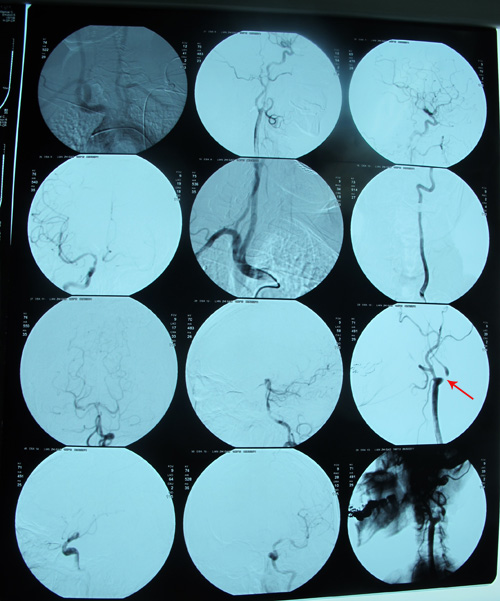

DSA:双侧颈内动脉分叉部位狭窄,以左侧为著,左侧颈内动脉起始段距开口1cm处呈细线样长约0.5cm重度狭窄99%。

颈动脉超声:双侧颈动脉中膜不均匀增厚伴斑块形成(多发);左侧颈动脉球部狭窄(50%-69%);双侧颈内动脉起始部狭窄(70-99%);左侧颈内 动脉内低回声,不除外血栓形成;右侧椎动脉椎间段血流速度减低。

DSA示:左侧颈内动脉分叉部位重度狭窄,狭窄率约为80%。